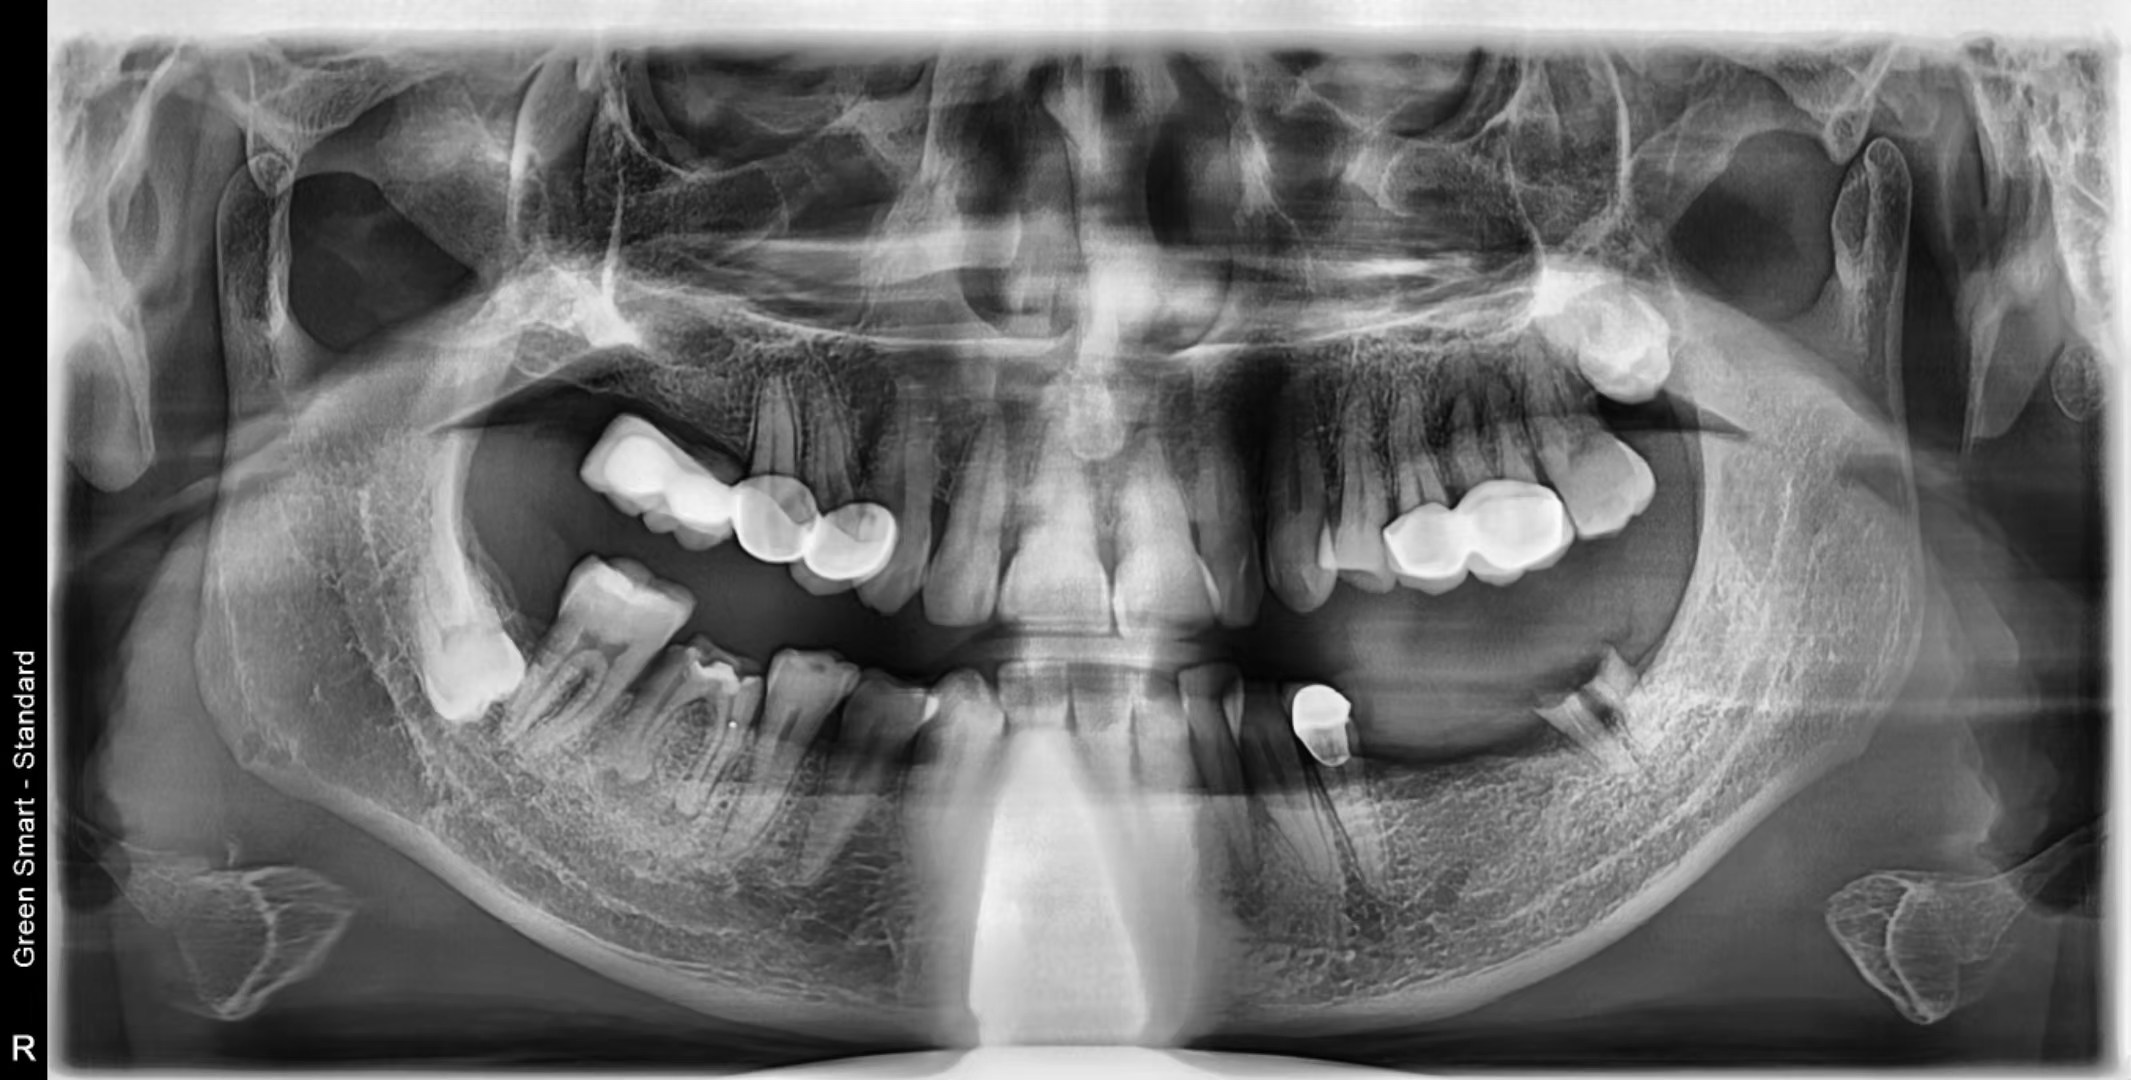

擅長多顆植牙及各類高難度複雜牙槽骨情況的植牙,案例二:

植牙前: